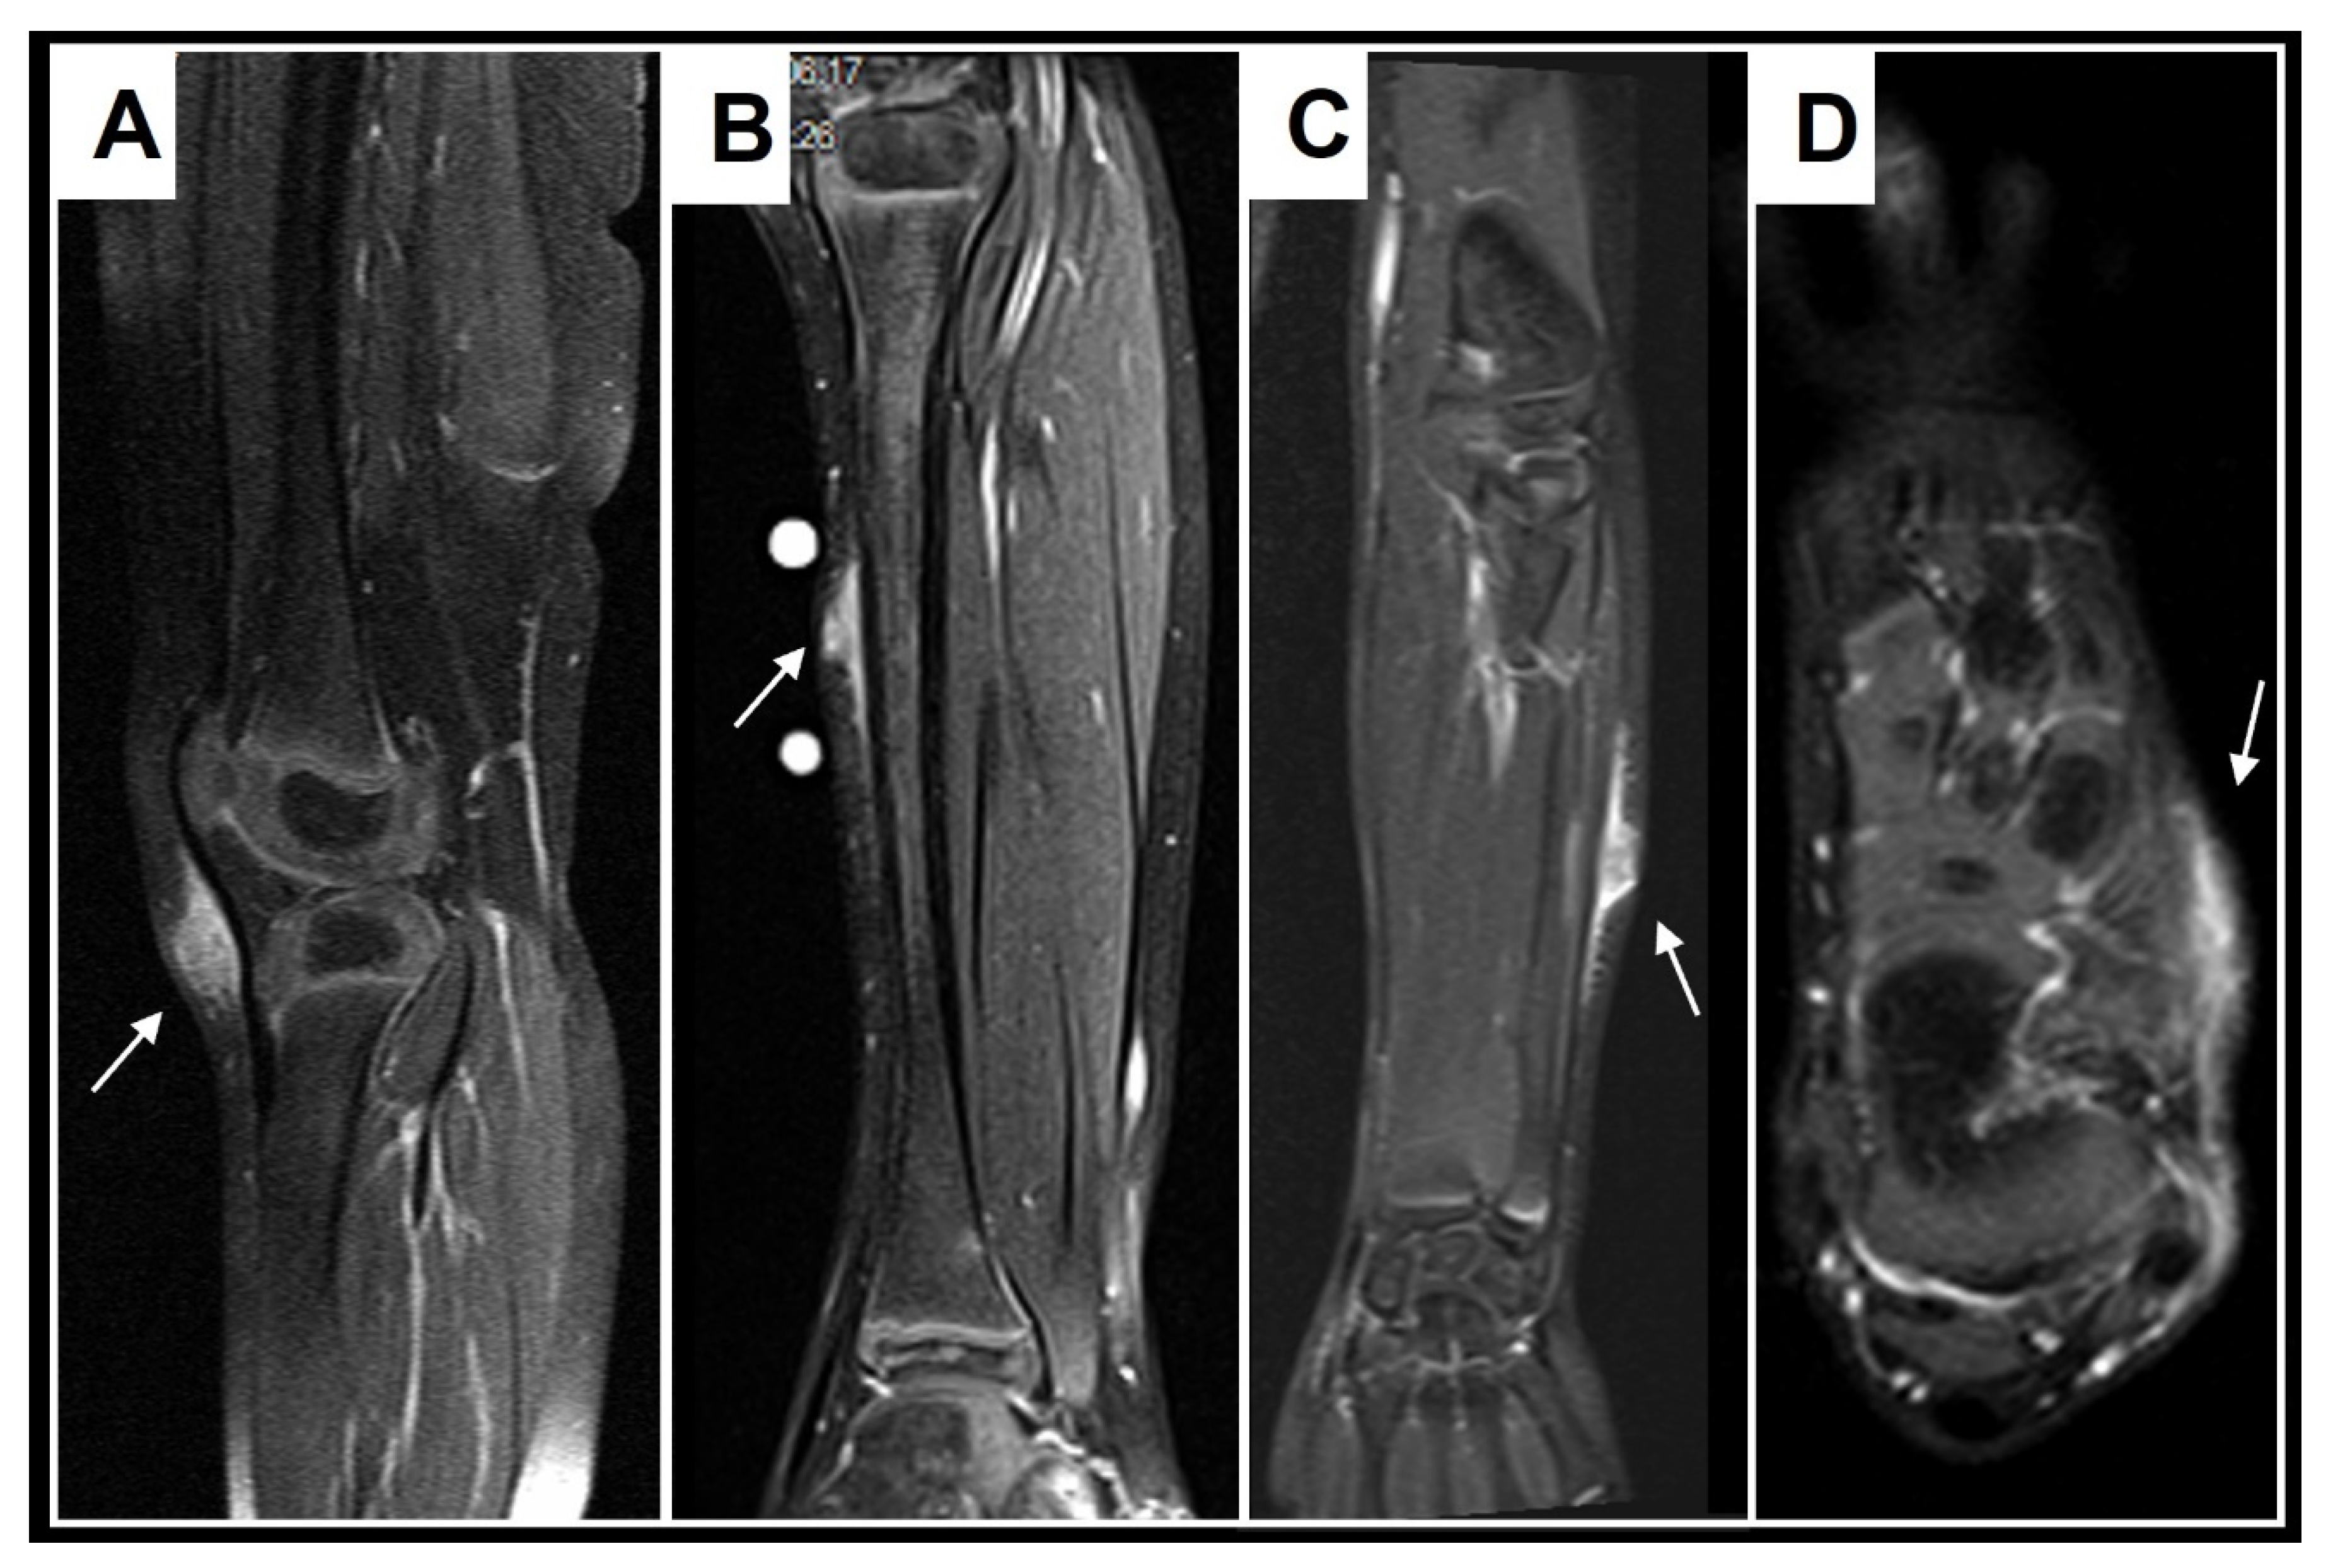

Figure 10.

These images show representative MRI slices through SGA (indicated by white arrows) at the knee (A); lower leg (B); forearm (C); and foot (D) in four different cases. Note that all SGA lesions show the typical epifascial extension with gradual rise of the lesion towards the more superficial tissues, which we have named the “epifascial cap” sign.